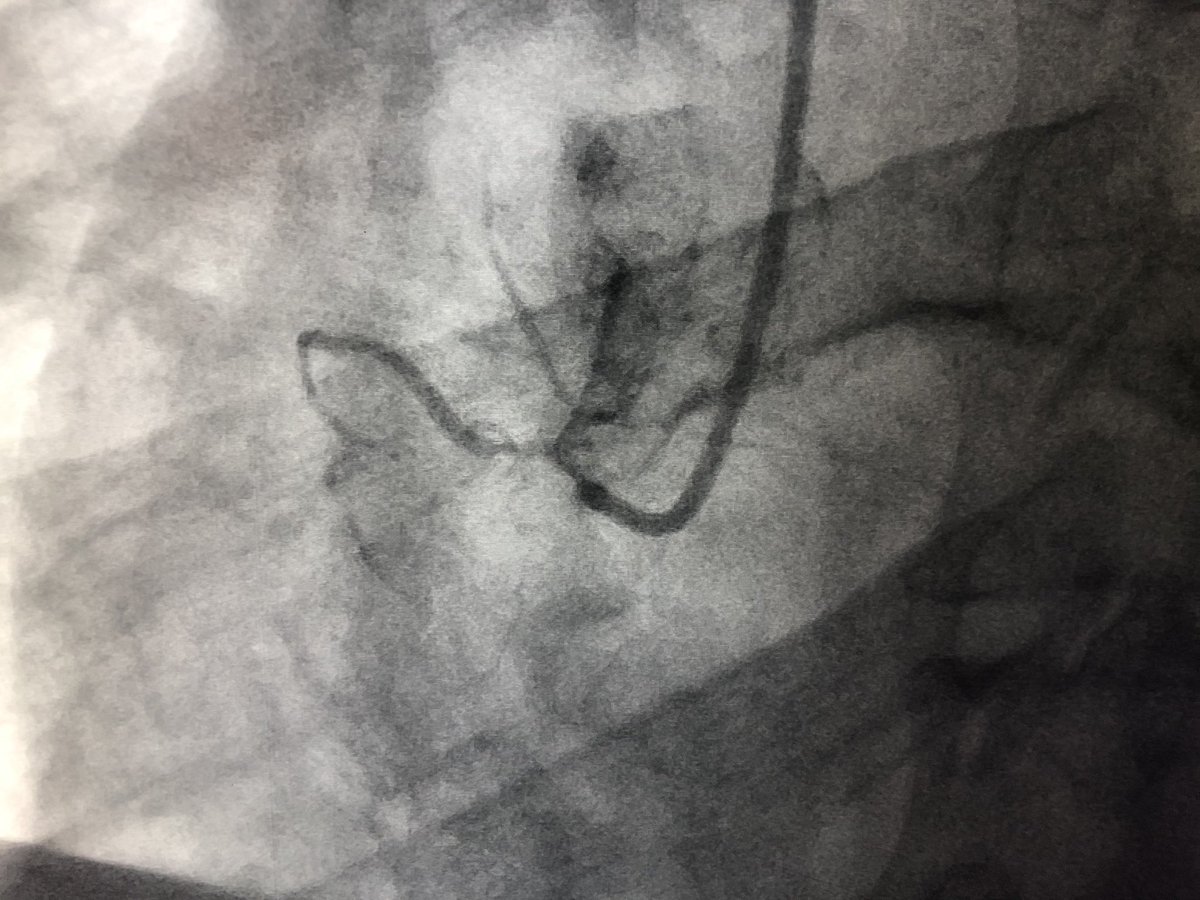

62 y/o male presents with NSTEMI. Boarded for cath in am. Prior to cath VT arrest and on vasopressors Findings at cath, severe LAD, CTO LCx, CTO RCA. LVEDP 34mmhg, EF 10%. Severe PAD. Rx with IC fellow sticks #PercAx Impella and IVUS guided revasc. Now off vasopressors.

DrAmirKaki's tweet image. 62 y/o male presents with NSTEMI.  Boarded for cath in am.  Prior to cath VT arrest and on vasopressors Findings at cath, severe LAD, CTO LCx, CTO RCA.  LVEDP 34mmhg, EF 10%.  Severe PAD.  Rx with IC fellow sticks #PercAx Impella and IVUS guided revasc.  Now off vasopressors.